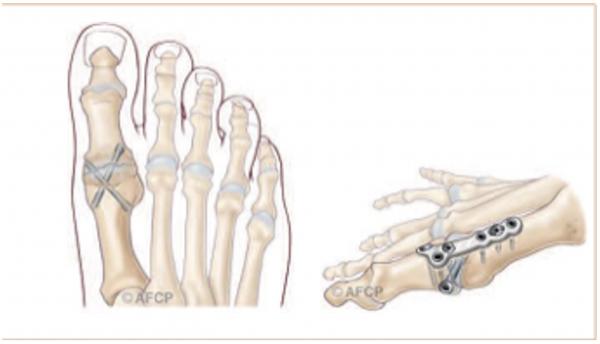

Chirurgical :

Les techniques « conventionnelles (ciel ouvert) » permettant, sous contrôle de la vue de corriger la déformation.

Au contraire, les techniques « percutanées » utilisent plusieurs incisions millimétriques, permettant le passage d’instruments spécifiques qui sont guidés sous la peau par un contrôle radiographique.

Anesthésie locorégionale et chirurgie ambulatoire

Pansement post op soit à changer par une infirmière à domicile ou à conserver en fonction de la technique opératoire

Chaussure médicale avec semelle rigide est prescrite avec appui autorisé mais le moins possible